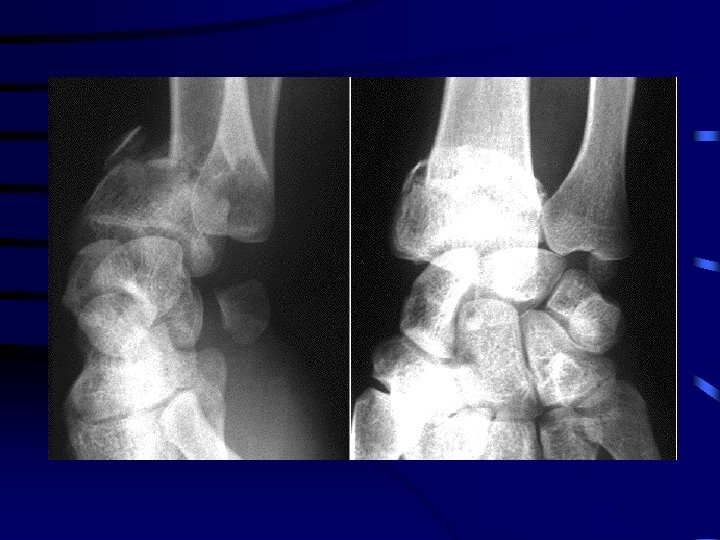

Traumatologie pédiatrique • L'enfant présente des types de fractures particuliers, en rapport avec la présence du cartilage de croissance ou dus à des propriétés mécaniques de l'os différentes de celles de l'adulte

1 Les décollements épiphysaires • Le trait de fracture traverse le cartilage de croissance. • Il en existe différents types selon que la fracture est articulaire ou extra-articulaire. • La consolidation est généralement rapide. • Le risque principal est l'épiphysiodèse (fermeture prématurée du cartilage de croissance).

• Salter 1 · Décollement épiphysaire pur : le trait passe entre épiphyse et métaphyse et détache l'épiphyse en bloc · Réduction généralement facile si elle est faite rapidement · Risque d'épiphysiodèse faible

• Salter 2 · Le trait sépare un fragment métaphysaire qui reste solidaire de l'épiphyse · Réduction généralement facile si elle est faite rapidement · La stabilisation est fréquemment orthopédique; l'ostéosynthèse est rarement nécessaire · Risque d'épiphysiodèse faible

• Salter 3 · Fracture articulaire qui détache un fragment épiphysaire · Risque d'épiphysiodèse important · La réduction doit être anatomique et se fait donc le plus souvent à foyer ouvert · L'ostéosynthèse peut se faire par des broches ou des vis en évitant de les faire traverser le cartilage de croissance

• Salter 4 · Fracture articulaire qui détache un fragment épiphysaire et un fragment métaphysaire · Risque d'épiphysiodèse important · La réduction doit être anatomique et se fait donc le plus souvent à foyer ouvert

• Salter 5 · Écrasement du cartilage de conjugaison qui fait suite à un mécanisme de compression par chute d'un lieu élevé. · La radiographie initiale est normale · Le diagnostic se fait donc à postériori en constatant une épiphysiodèse